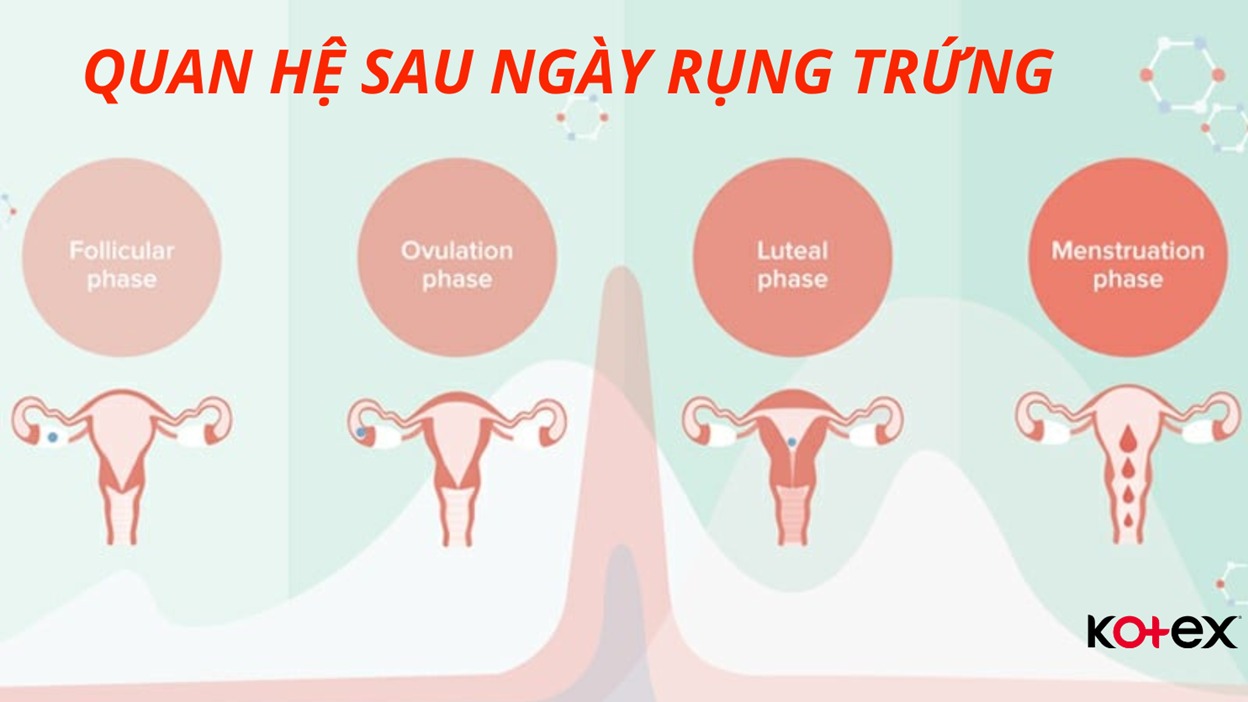

Chào bạn thân mến, bạn có bao giờ tự hỏi làm thế nào để tính thời gian rụng trứng một cách chính xác nhất không? Việc hiểu rõ chu kỳ rụng trứng của bản thân không chỉ là kiến thức quan trọng về sức khỏe giới tính, mà còn là một cách tuyệt vời để […]

Chào bạn yêu quý, chúng ta lại gặp nhau rồi. Hôm nay, chúng ta sẽ cùng nhau trò chuyện về một chủ đề rất được quan tâm, đặc biệt là với những ai đang mong muốn chào đón một thành viên mới trong gia đình: đó là cách tính ngày rụng trứng thụ thai. Hiểu […]

Chào bạn, có lẽ bạn đang băn khoăn về một câu hỏi rất quan trọng: trứng không rụng có thụ thai được không? Đây là một thắc mắc cực kỳ phổ biến mà Chuyenseg nhận được, và chị hiểu cảm giác lo lắng, bối rối khi tìm kiếm câu trả lời. Trong hành trình khám […]

Chào bạn thân mến, Tại Chuyenseg, chúng mình hiểu rằng hành trình khám phá và làm chủ cơ thể mình là một điều vô cùng thú vị và quan trọng. Đặc biệt, việc tính ngày rụng trứng chính xác là một trong những kiến thức nền tảng giúp bạn hiểu sâu hơn về chu kỳ […]

Chào bạn của Chuyenseg, chị biết có rất nhiều bạn nữ đang thắc mắc về chu kỳ của mình, đặc biệt là việc trứng đã rụng siêu âm có thấy không. Đây là một câu hỏi rất hay và quan trọng, nhất là khi chúng ta muốn hiểu rõ hơn về cơ thể mình, hoặc […]